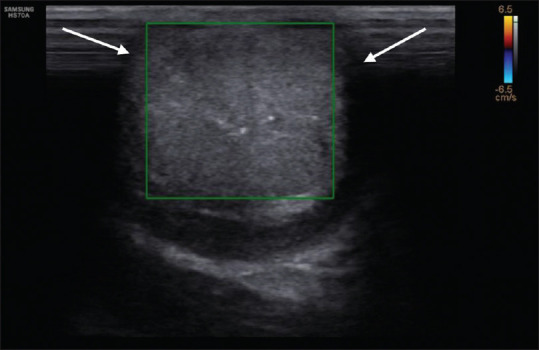

Testicular torsion is an emergency clinical situation. It is rarely seen associated with ureterocele. We presented a case report where a 15-year-old adolescent boy presented with severe testicular and vague abdominal pain was found on imaging to have testicular torsion and ureterocele. Ultrasonography Doppler and computed tomography imaging are being described.

睾丸扭转是一种紧急的临床情况。它很少与输尿管囊肿合并。我们提出一个病例报告,一个15岁的青春期男孩表现为严重的睾丸和模糊腹痛,在影像学上发现有睾丸扭转和输尿管膨出。介绍了超声多普勒和计算机断层成像。